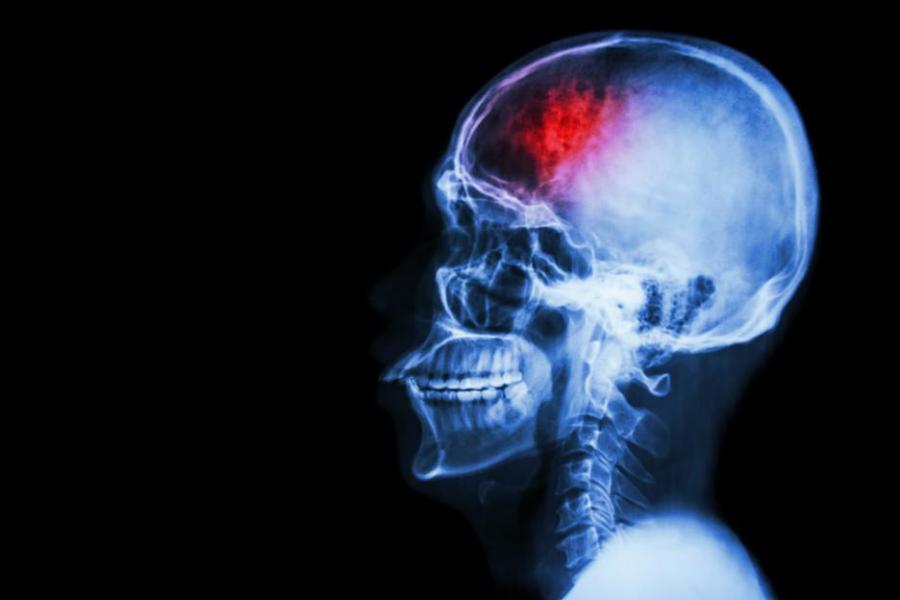

Ето как да постъпим, ако някой около нас получи инсулт

Неврохирурзите твърдят, че ако имат възможност да оперират пациент, който е получил инсулт в рамките на три часа, всички шансове са налице, че той ще може да се възстанови. Не винаги обаче е лесно да се разпознаят всички признаци на мозъчния удар. Особено от човек, който няма каквито и да е медицински познания.